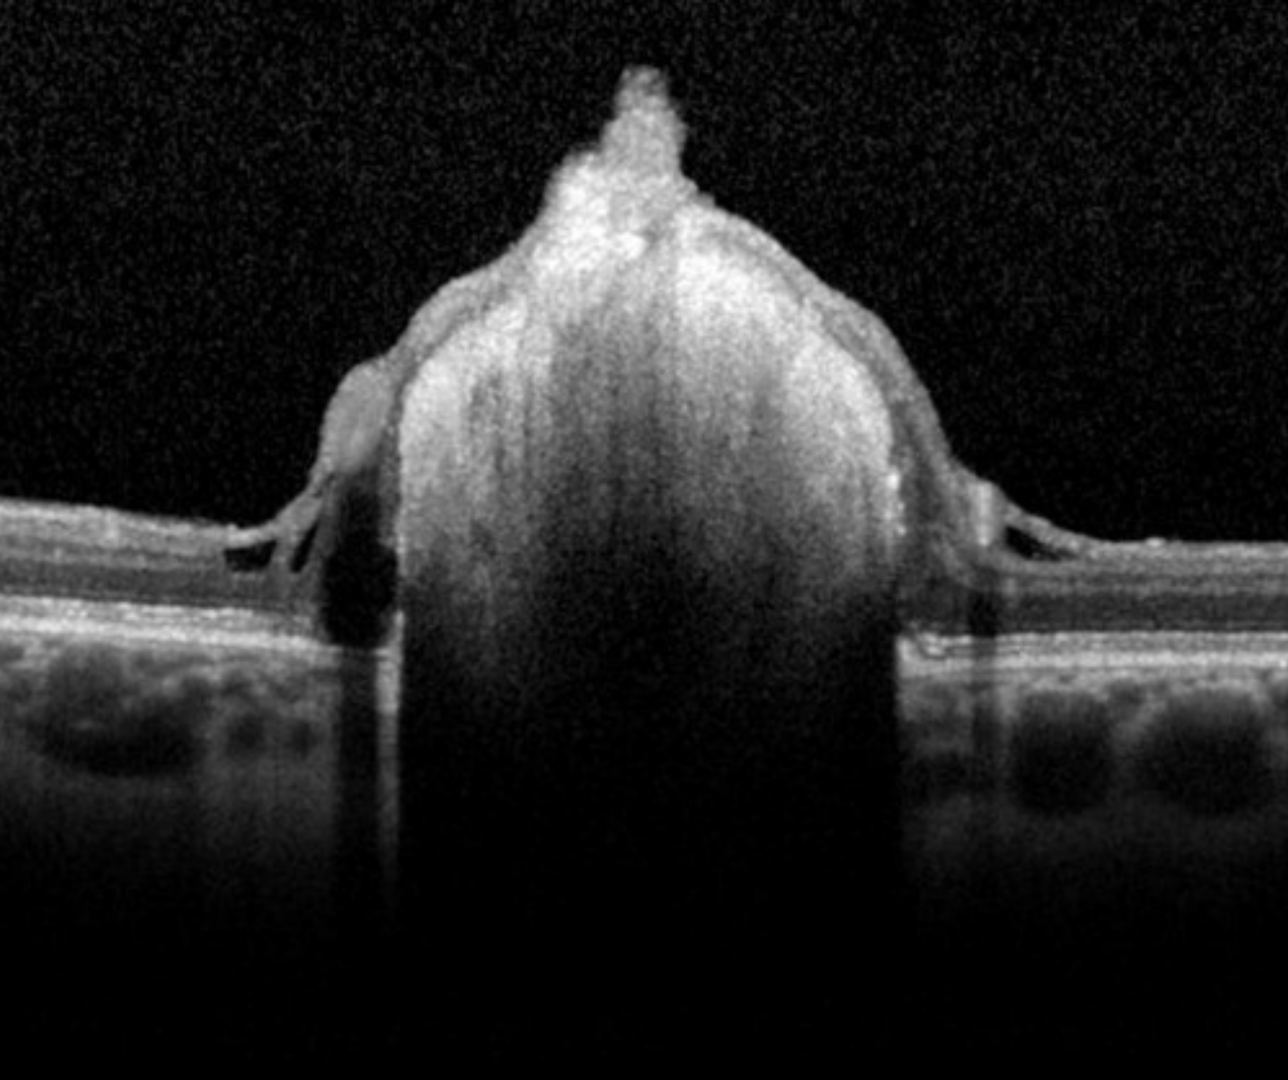

OCT imaging shows an intraretinal hyper-reflective elevation with posterior shadowing. With increasing calcification, moth eaten spaces can be seen internally.